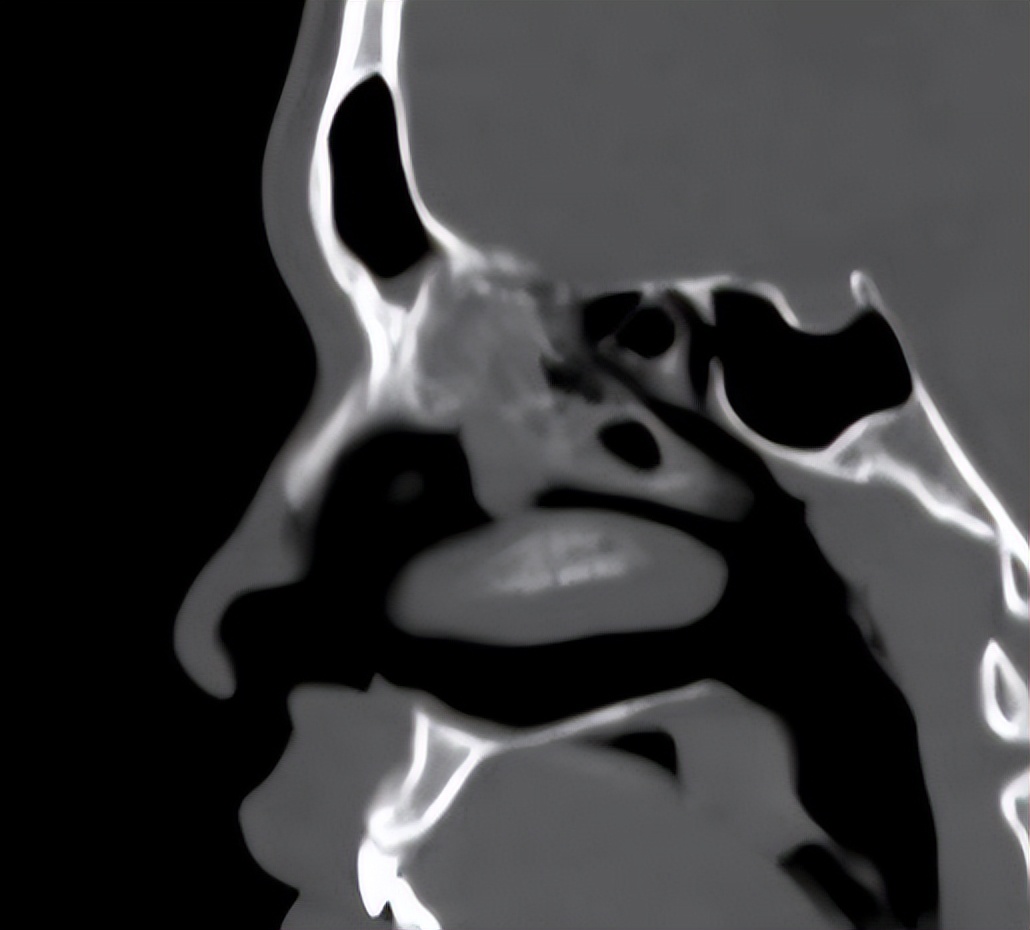

但容易反复,这次有时间找到耳鼻喉郑立岗医生,检查后考虑是过敏性鼻炎为主,由于长期的控制不佳,导致伴发了鼻窦炎和鼻息肉,这种情况一般建议手术治疗效果会更好一些。

和家人商量后决定做手术治疗,就入院了。这次安排的是鼻内镜鼻窦炎微创手术和下鼻甲手术,插管全麻后就开始了手术。在鼻内镜下切除鼻息肉和开放鼻窦后,清除了炎症病变,并做了鼻甲的射频治疗,解决鼻炎的问题,整个的手术非常的顺利,用时约一个多小时。术后查房患者无明显的不适,无手术相关的并发症。